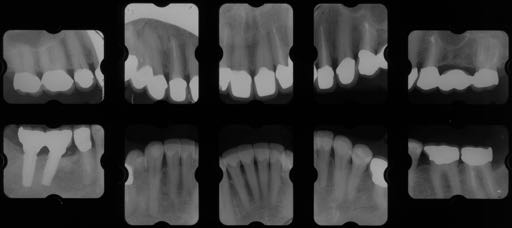

Degree of Difficulty +++

非常に治療難易度の高いケースである